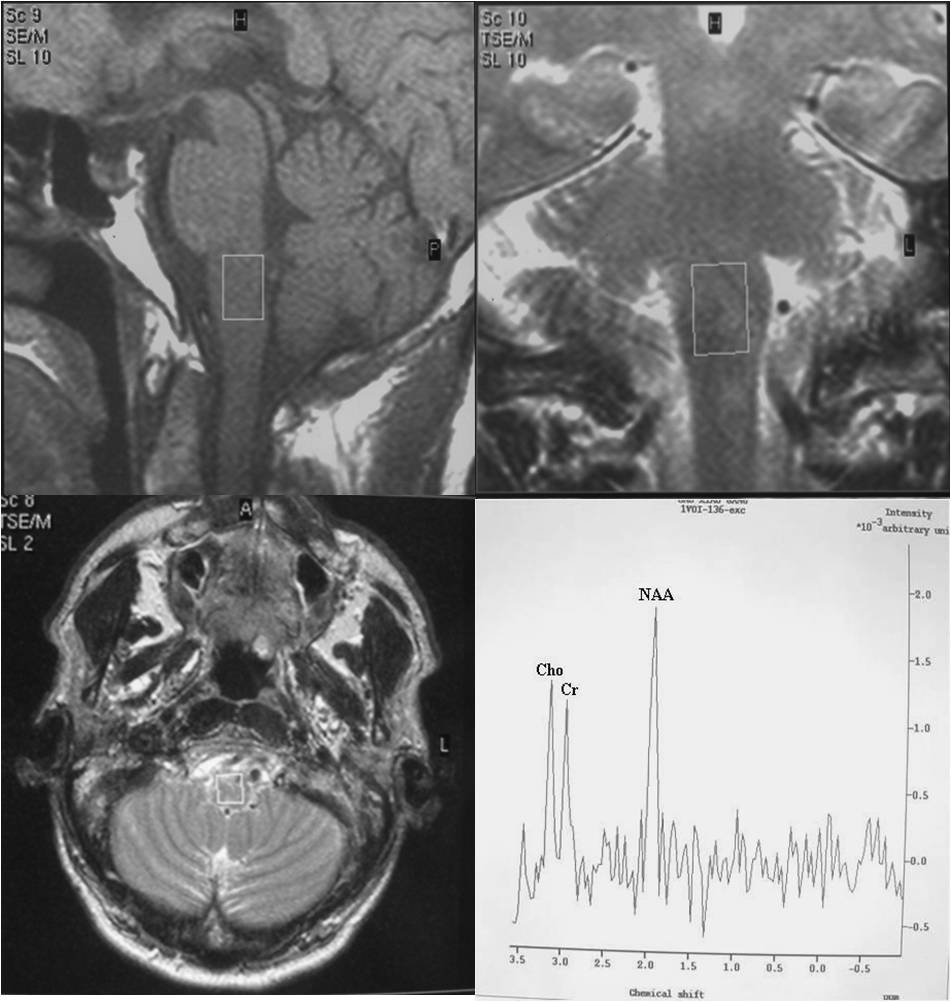

Objective: To use 1.5T 1H-MRS as a research tool in vivo and demonstrate the feasibility of obtaining long-echo 1H MR spectra in small volumes like substantia nigra (SN) and medulla oblongata (MO) in healthy volunteers and patients with Parkinson's disease (PD) and observe the clinical correlations.

Subjects and Methods: Twenty patients of the idiopathic Parkinson’s disease (IPD) were recruited from the Out Patient Department of Neurology. Additionally, 14 age-matched healthy subjects were taken as controls group. After baseline evaluation, the patients satisfying inclusion and exclusion criteria underwent 1H-MRS study. All MR examinations were performed on a 1.5 T system (Philips Gyroscan Intera, Netherlands) using a standard quadrature head coil.

Results: We succeeded to achieve 74.19% and 77.42% of spectra from MO and SN of both PD and control groups. MO showed slightly weak negative result to total UPDRS and UPDRS- II, but no significant correlation was found between metabolites and clinical indexes in MO. The result also showed no significant correlations between H&Y scale and metabolites in MO and SN of PD patients. But there was a significant correlation between H&Y, NAA/Cr and Cho/Cr in SN.